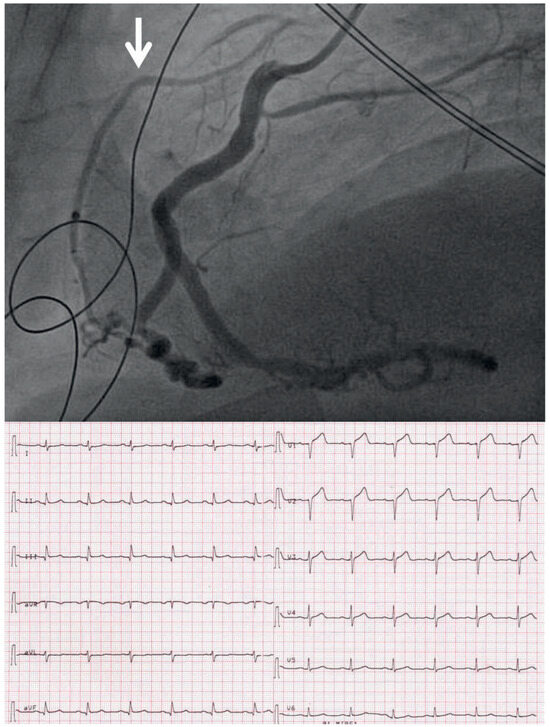

Infarct or Pericarditis?

by Sebastian Rogowski, Flurina Arquint, Hans Rickli, Niklas F. Ehl and Micha T. Maeder

Cardiovasc. Med. 2015, 18(3), 107; https://doi.org/10.4414/cvm.2015.00314 - 18 Mar 2015

A 56-year-old man was referred at 5 a.m. with severe central chest pain radiating into the left arm, which had awoken him from sleep one hour previously [...] Full article